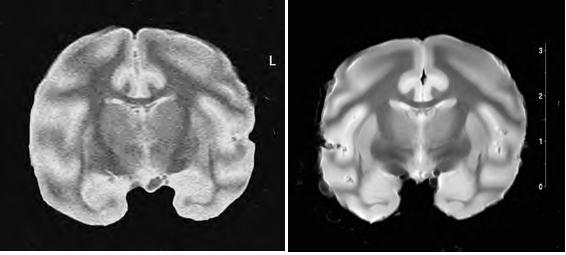

現在、先端計測分析技術・機器開発の重要性が認識されているが、国産の技術によってMRIという重要な計測機器の上位機種が開発された事は、極めて重要な意義を持つ。本機は既に国内で2台が運用開始されており、解像度50 m以下の画像が撮られている(図2)。このような高磁場MRIの基本要素が開発されたことで、これら装置を活用したわが国のバイオテクノロジー開発がいっそう加速する事が期待される。

図2 同条件下で取得された赤毛サル摘出脳の断面画像

(左)人体用1.5T機、(右)7T機